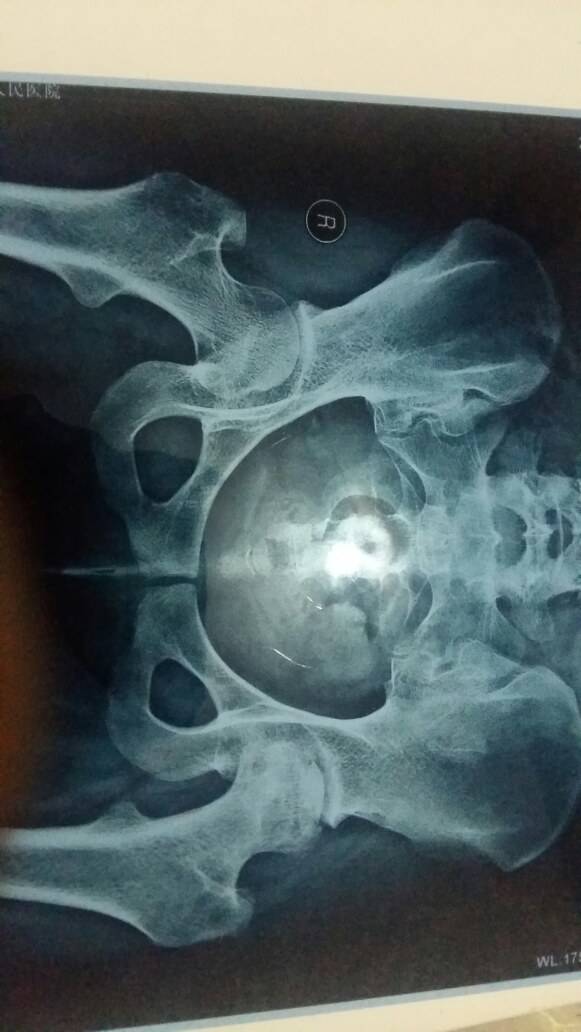

这是怎么看的啊,是哪个位置塌啊。。

你的左边比较严重,但是也不是太严重,你注意不要负重,拄拐在治疗下,或者可以好转或者延缓下塌陷时间

看不懂片子,我的也在慢慢塌